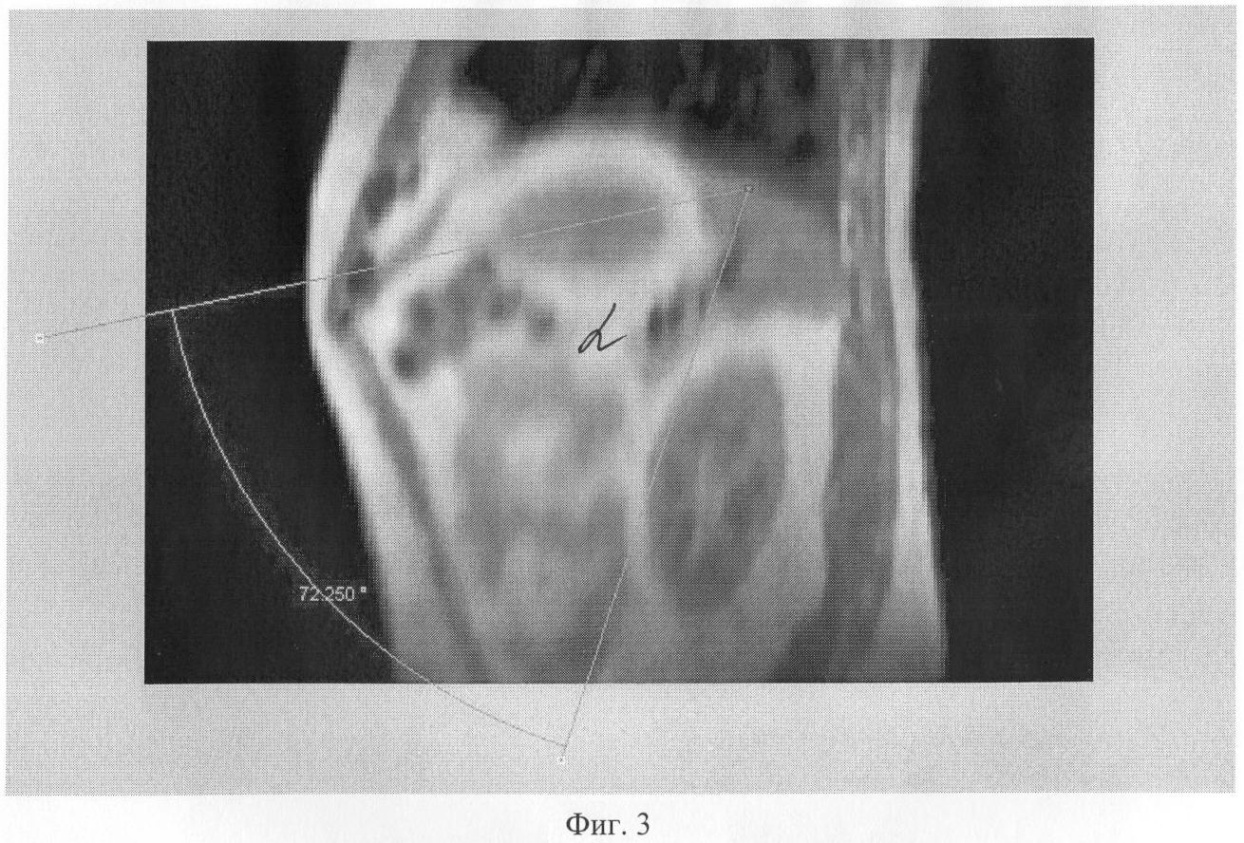

На Фиг.3 показан угол в сагиттальной проекцией с ориентацией на сосудистый пучок селезенки.

Измерялись углы между оптической осью эндоскопа (ось операционного действия) и манипуляционными портами и УОД – углы , , , при этом вершина угла ориентировалась на сосудистую ножку селезенки примерно в 2 см от ее ворот (Фиг.1-3) и на оба полюса селезенки (Фиг.6). Углам приданы следующие обозначения:

В прямой проекции (Фиг.1) выбирают направление в свободном пространстве между органами брюшной полости с прицелом на сосудистый пучок селезенки, точку А, в пределах 25-90° между осями инструментов, программа запоминает эту позицию. Выбирают положение векторов в аксиальной проекции (Фиг.2), затем в сагиттальной Фиг.3. Строят итоговое объемное трехмерное изображение совмещением трех срезов и векторов с проекцией на кожу (Фиг.4, 5). При этом величину углов можно задавать автоматически, векторы перемещаются в новое положение и находят новые рабочие точки Г, Д, Е (Фиг.5) для введения инструментов. Проверяют длину новых векторов, проверяя, не превышает ли их длина рабочую длину инструментов. Если три условия выполнения лапароскопической операции не получены, то вновь производят подбор новых точек, изменяя величину углов. Проводят контрольное позиционирование на крайние точки зоны операции на органе-мишени Б и В (Фиг.6). Строят биссектрису угла . Проверяют длину векторов от точек Б и В на поверхности органа до вновь найденных точек на поверхности тела Г, Д, Е, она не должна превышать рабочую длину инструментов. Проверяют величину углов. Если условия не выполняются, то вновь изменяют величины углов , , и находят оптимальный вариант. После того как новые точки для введения инструментов найдены на визуализированной поверхности, переносят их на кожу пациента, ставя новые метки другим маркером, например зеленкой в точках Г, Д, Е. Троакары в ходе операции вводят во вновь определенные точки.